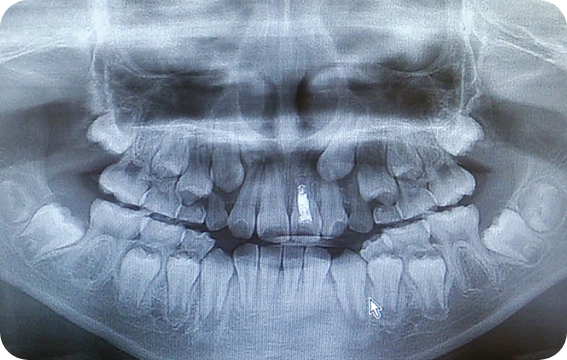

2.精密検査

歯型の採取、レントゲン撮影などを通じて、歯や顎の状態を詳しく調べます。このデータをもとに最適な治療計画を立てます。